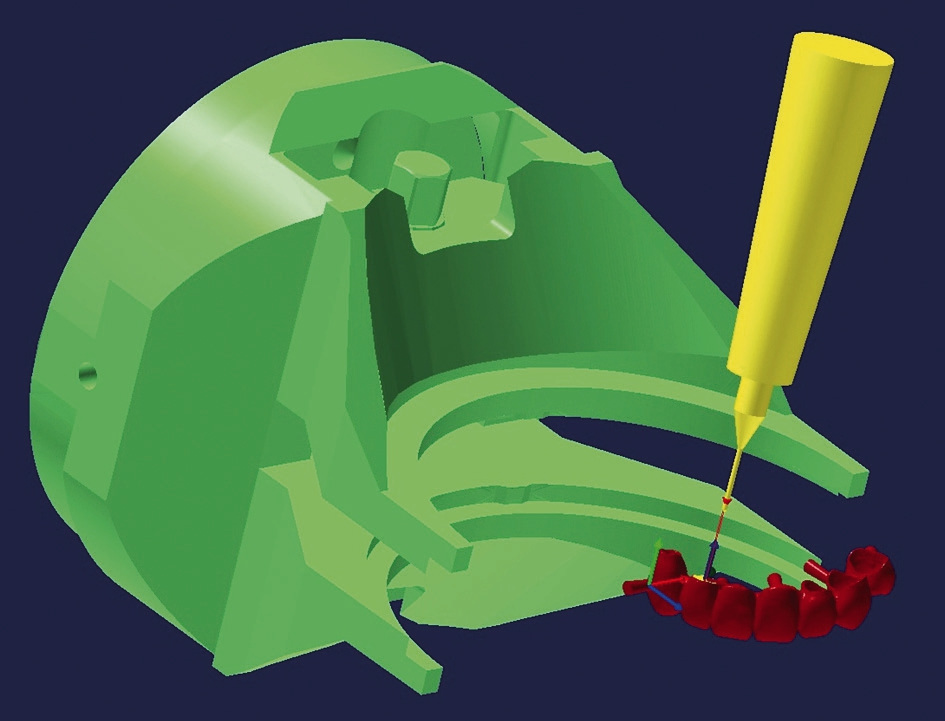

Ginge man für die Herstellung von Eierschalenprovisorien rein analog vor, müssten am Gipsmodell alle Zahnflächen leicht subgingival mit minimaler Tiefe vorpräpariert werden, das würde einen großen Aufwand bedeuten. Diese Präparation findet nun digital statt, was wir als deutlich genaueres und auch schnelleres Arbeiten erfahren.

Nach der digitalen Modellation werden die Konstruktionsdatensätze in eine CAM-Software geladen, wir nutzen hierzu SUM 3D (MB-Maschinen, Biebergemünd) und hyperDENT (Follow-me! Technology, München). Mit dieser Software erfolgt zunächst das Nesting (Abb. 7), d. h. das Platzieren der Konstruktion im jeweiligen Blank. Hier muss sowohl auf die Höhe als auch Lage geachtet werden. Danach wird die Arbeit berechnet, d. h. es werden Templates („Kochrezepte“ für den Fräsvorgang) definiert (Abb. 8). Durch diese erhält die jeweilige Fräsmaschine die Informationen, die zum Fräsen benötigt werden, z. B. die maximalen Vorschübe, die Anstellwinkel oder die zu verwendenden Fräswerkzeuge (Abb. 9). Nachdem sichergestellt ist, dass die richtigen Materialien und Werkzeuge in der Maschine eingespannt sind, wird der Fräsbefehl an die Maschine übermittelt und der Fräsvorgang gestartet (Abb. 10).